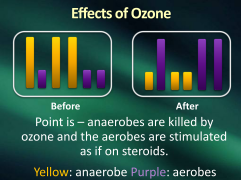

The modern dentist considers ozone

which anaerobes can not condone

But aerobes ask for another dose

I’m on steroids, so they boast